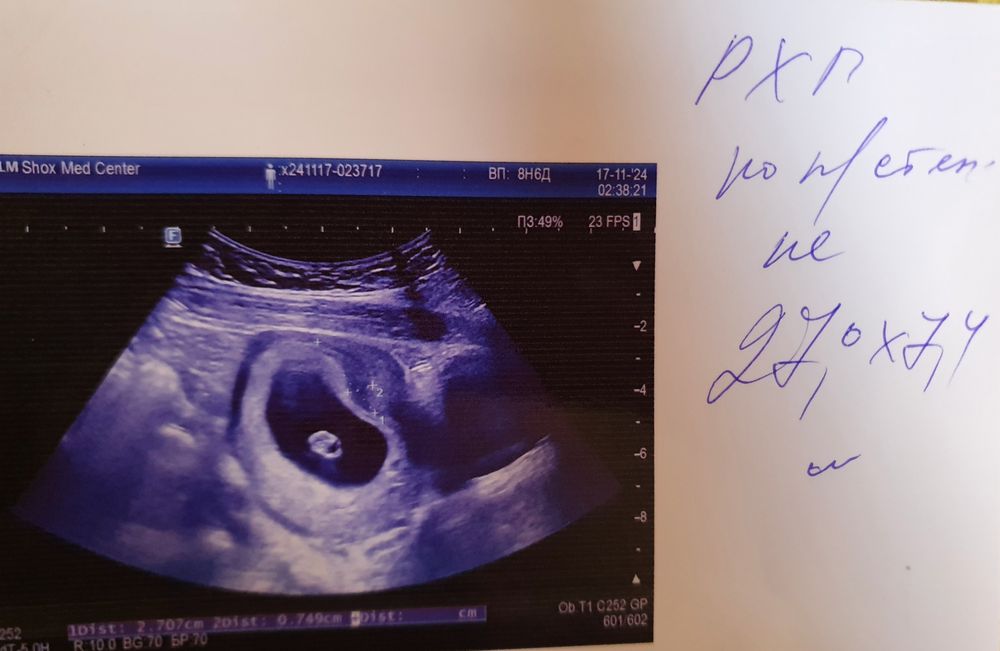

8.6 недель Отслойка и гематома 27 мм,после полового акта

Девочки,у кого было что то похожее,что прописали как действовали,впервые после зачатия решили заняться половым актом,как хлынула алая кровь,бегом на узи,поставили гипер тонус ,гематому с отслойкой,фото прилагаю,написала гинекологу сказал дюфастон и дицинон вколоть,выделения прекратились,а что дальше как это опасно для плода,через сколько рассосётся?